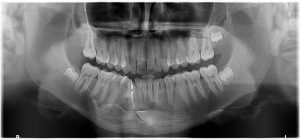

Removal of impacted teeth Surgical removal of all wisdom teeth and impacted teeth. An impacted tooth is a tooth that is unable to erupt into its normal position in the jaw. This is usually caused by the tooth becoming blocked in-between two adjacent teeth or by the tooth being formed in an abnormal position. The most commonly affected teeth are the wisdom teeth/third molars and the canines. Wisdom teeth are the last teeth to erupt in your mouth, usually between the ages of 17 and 25. In ancient times, the rough diet people followed resulted in the excessive wear of their teeth. The normal drifting of the teeth to compensate for this wear ensured that space was available for most wisdom teeth to erupt by adolescence. However, our modern diet is softer, so wear is minimal so drift is also minimal, resulting in less space for wisdom teeth to erupt naturally. Why remove them? If a wisdom tooth doesn’t have room to grow (impacted wisdom tooth), this may result in pain, infection or other dental problems. The patient will then probably need to have it removed. The extraction of wisdom teeth is generally necessary when they are prevented from properly erupting within the mouth. Poor alignment of wisdom teeth can crowd or damage adjacent teeth, the jawbone, and nerves. Wisdom teeth that lean toward the second molars make those teeth more vulnerable to decay by entrapping plaque and debris. This can lead to swollen and sore gums (pericoronitis), tooth decay, jaw stiffness and infection. Partially erupted teeth are also more prone to tooth decay and gum disease because their hard-to-reach location and awkward positioning makes brushing and flossing difficult. Other issues that can arise include the formation of tumours or cysts around the impacted tooth. This can in turn result in permanent damage to the jawbone and other, healthy teeth. What happens next? Dr Ehlers will exam and take an X-Ray of your mouth. This will allow him to see the extent of the impaction or eruption and to plan a course of action suitable to your particular case. Depending on his assessment Dr Ehlers will advise you on whether it is better to have a procedure where local anaesthetic (you will be awake during the procedure) is used or general anaesthetic (you will be asleep during the procedure). During a local anaesthetic procedure your gum area will be numbed around the wisdom tooth/teeth, so you will feel no pain. In addition, Dr Ehlers may opt to use a sedative which will help you to relax during the procedure. During the procedure, the tooth may be cut into smaller parts to make it easier to remove through the opening. There’s less need to make an incision if the tooth has already erupted through the gum. Should you need to be admitted to hospital as a day patient, you will be given a general anaesthetic which will make you sleep. Read more about after-procedure care

How a tooth is extracted With the help of x-rays, your oral surgeon will determine the best way to remove the tooth or teeth. There are two types of extractions: